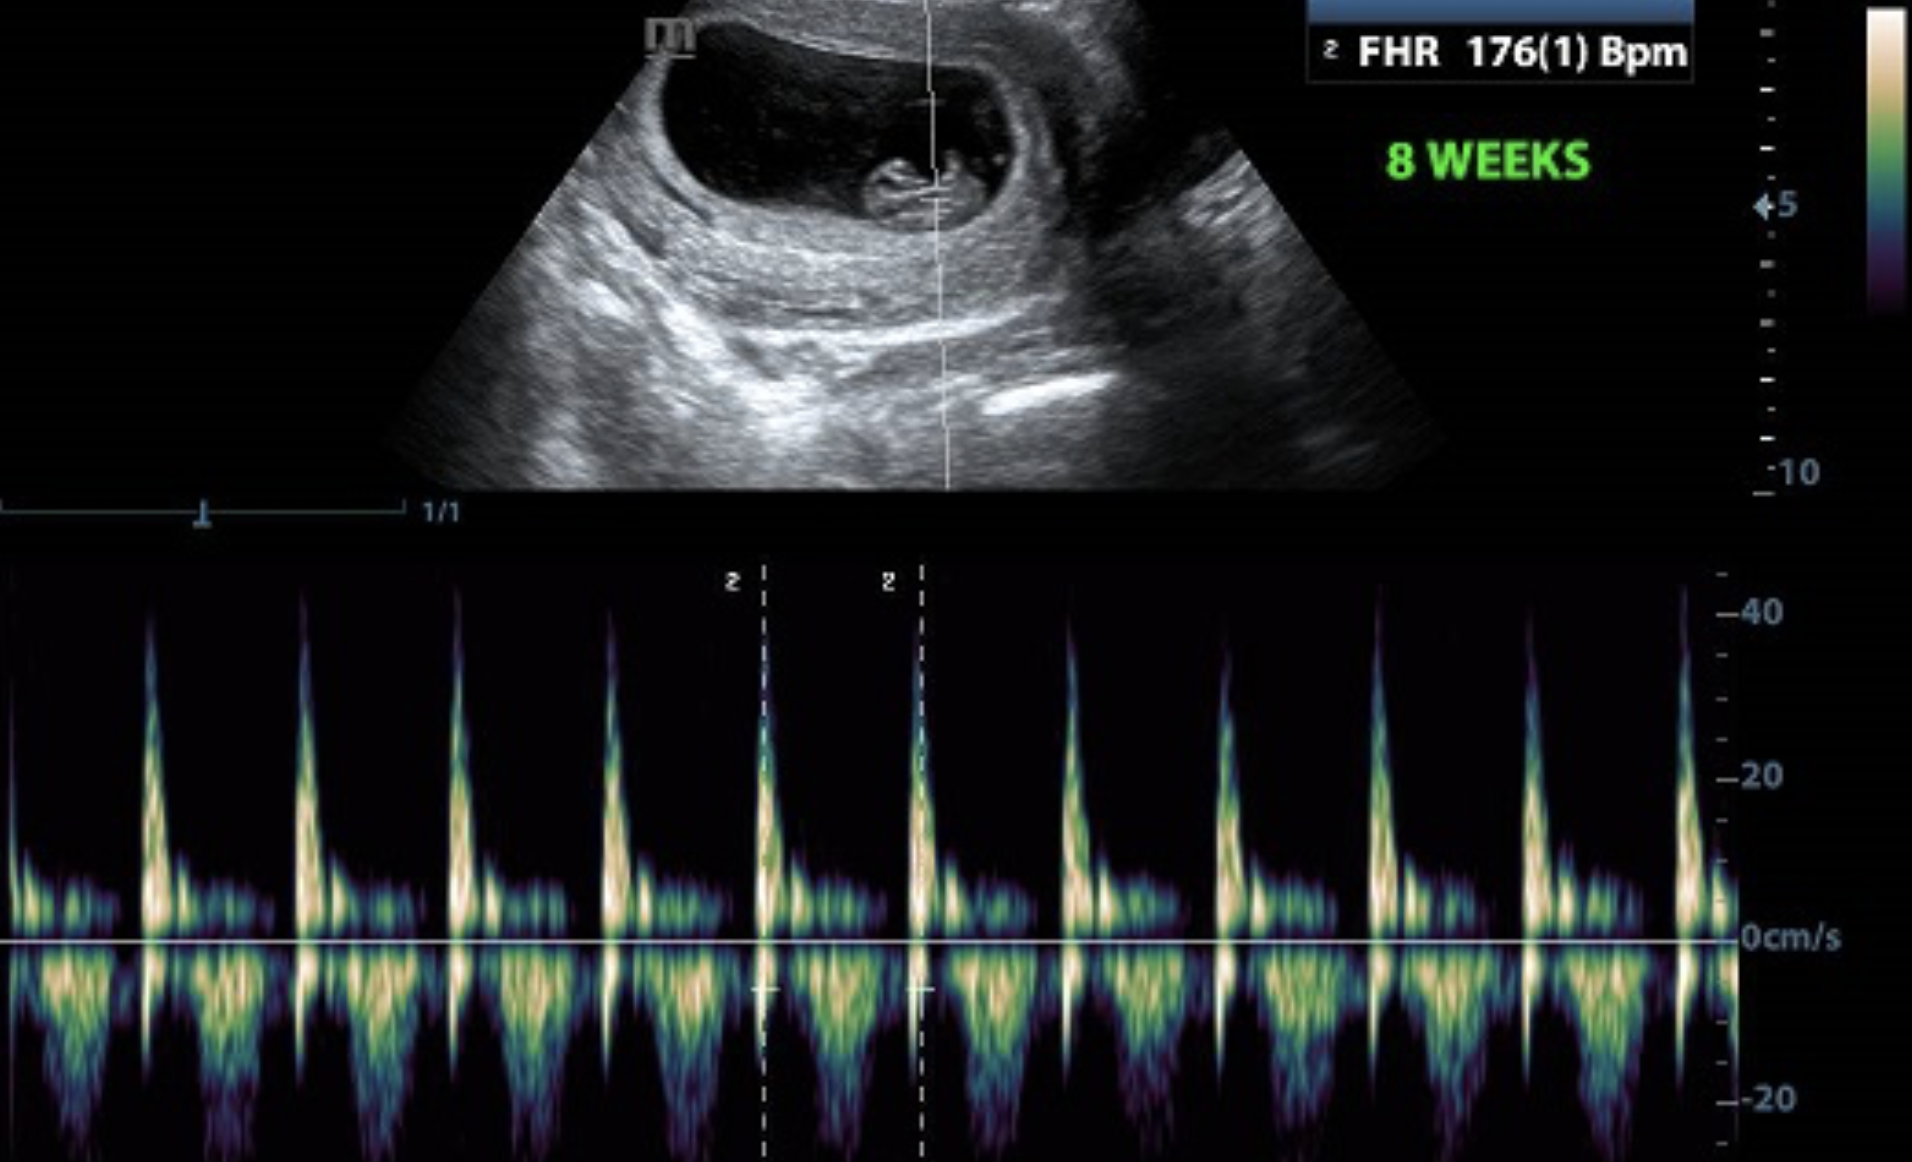

The current attempts of states to devise local workarounds that evade the constitutional right of access to abortion–and guarantee of access as a binding precedent of the court–has come up against loggerheads with the concept of the freedom of “unborn children” posing pressing questions of what is a “compelling interest” of the state in a fetus before life can be sustained outside of the womb. The recent focus of on the heartbeat, or rather the appearance or perception of the heartbeat, as an index or sign of value–if without basis in medical science–has become a new basis to increase the burdens on women in most states to access maternal health. For the designation of cardiac contractions as evidence of a “person” or a soul that in the interest to the state to protected is, in fact, a terrifying smokescreen for the radical contraction of a pregnant women’s rights.

Cardiac Activity in a Fetus of Eight Weeks

For by redefining the fetus as a “life,” with freedoms and liberties attached and pursuant, Iowa’s legislature abandoned the standard of viability outside of the womb, asserting that the unborn is a person, and abortion tantamount to killing a life, as if “the burdens of carrying a child to term [could] justify the killing of a child,” per the lawyer representing the state of Iowa in 2018. It takes arguments of the potentiality of the unborn to the extreme, not discussing the Thomistic idea of potentiality of human life recently promoted by Catholic theologians as a middle ground, but mapping the heart of the matter–the heartbeat–the visual evidence of personhood. Fueled by the affective relations of ultrasounds that offer the “science” that seems to sever the personhood of the “unborn child” from the standard of viability that had set the threshold for up to what point the protection of a woman’s access to abortion was permitted by constitutional law. The rise of proscribed ultrasounds across multiple states reflect the new focus on personhood and heartbeats, whose mandated display and discussion provided a preventive basis for persuading those seeking abortion to forego the procedure.

Cast as a “Right to Know” legislation that was introduced in Pennsylvania in 2012 mandating all women who are seeking abortions to view the ultrasound designed to determine the gestational age of the unborn fetus–a means of placing the abortion in a window of viability–offered all women seeking an abortion the “right” see the image, and to hear the heartbeat, offering a new way to map life and epigenetic questions of ensoulment around the “beating” of the heart, although no ultrasound was mandated in states protecting abortion rights.

The imaging tools of the ultrasound after all transformed the fetus to a “baby’s head” and “baby’s heart” able to be recognized on the screen, and indeed labeled for identification, in ways that seemed to deliver a deeper truth, in an age when we have difficulty distinguishing representation and reality, expanding the case in the courtrooms that the presence of a fetal heartbeat offered incontrovertible evidence in a court of law that a “a human child with a heartbeat is a living child,” even if few judges in Iowa were ready to hear the argument, if the state’s lawyer refused to accept that the fetus with a heartbeat was a “potential life”